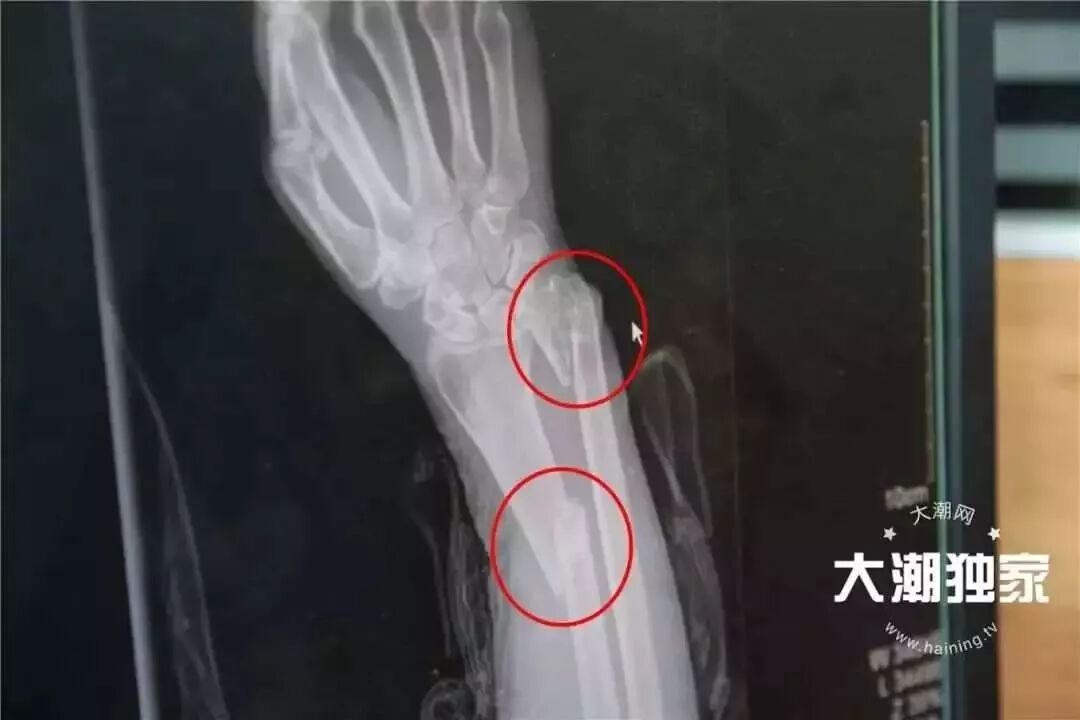

老太当时右手腕有点骨折

不过额头有6-7公分伤口

右手前臂外侧有1-2公分伤口

右前臂有2处骨折